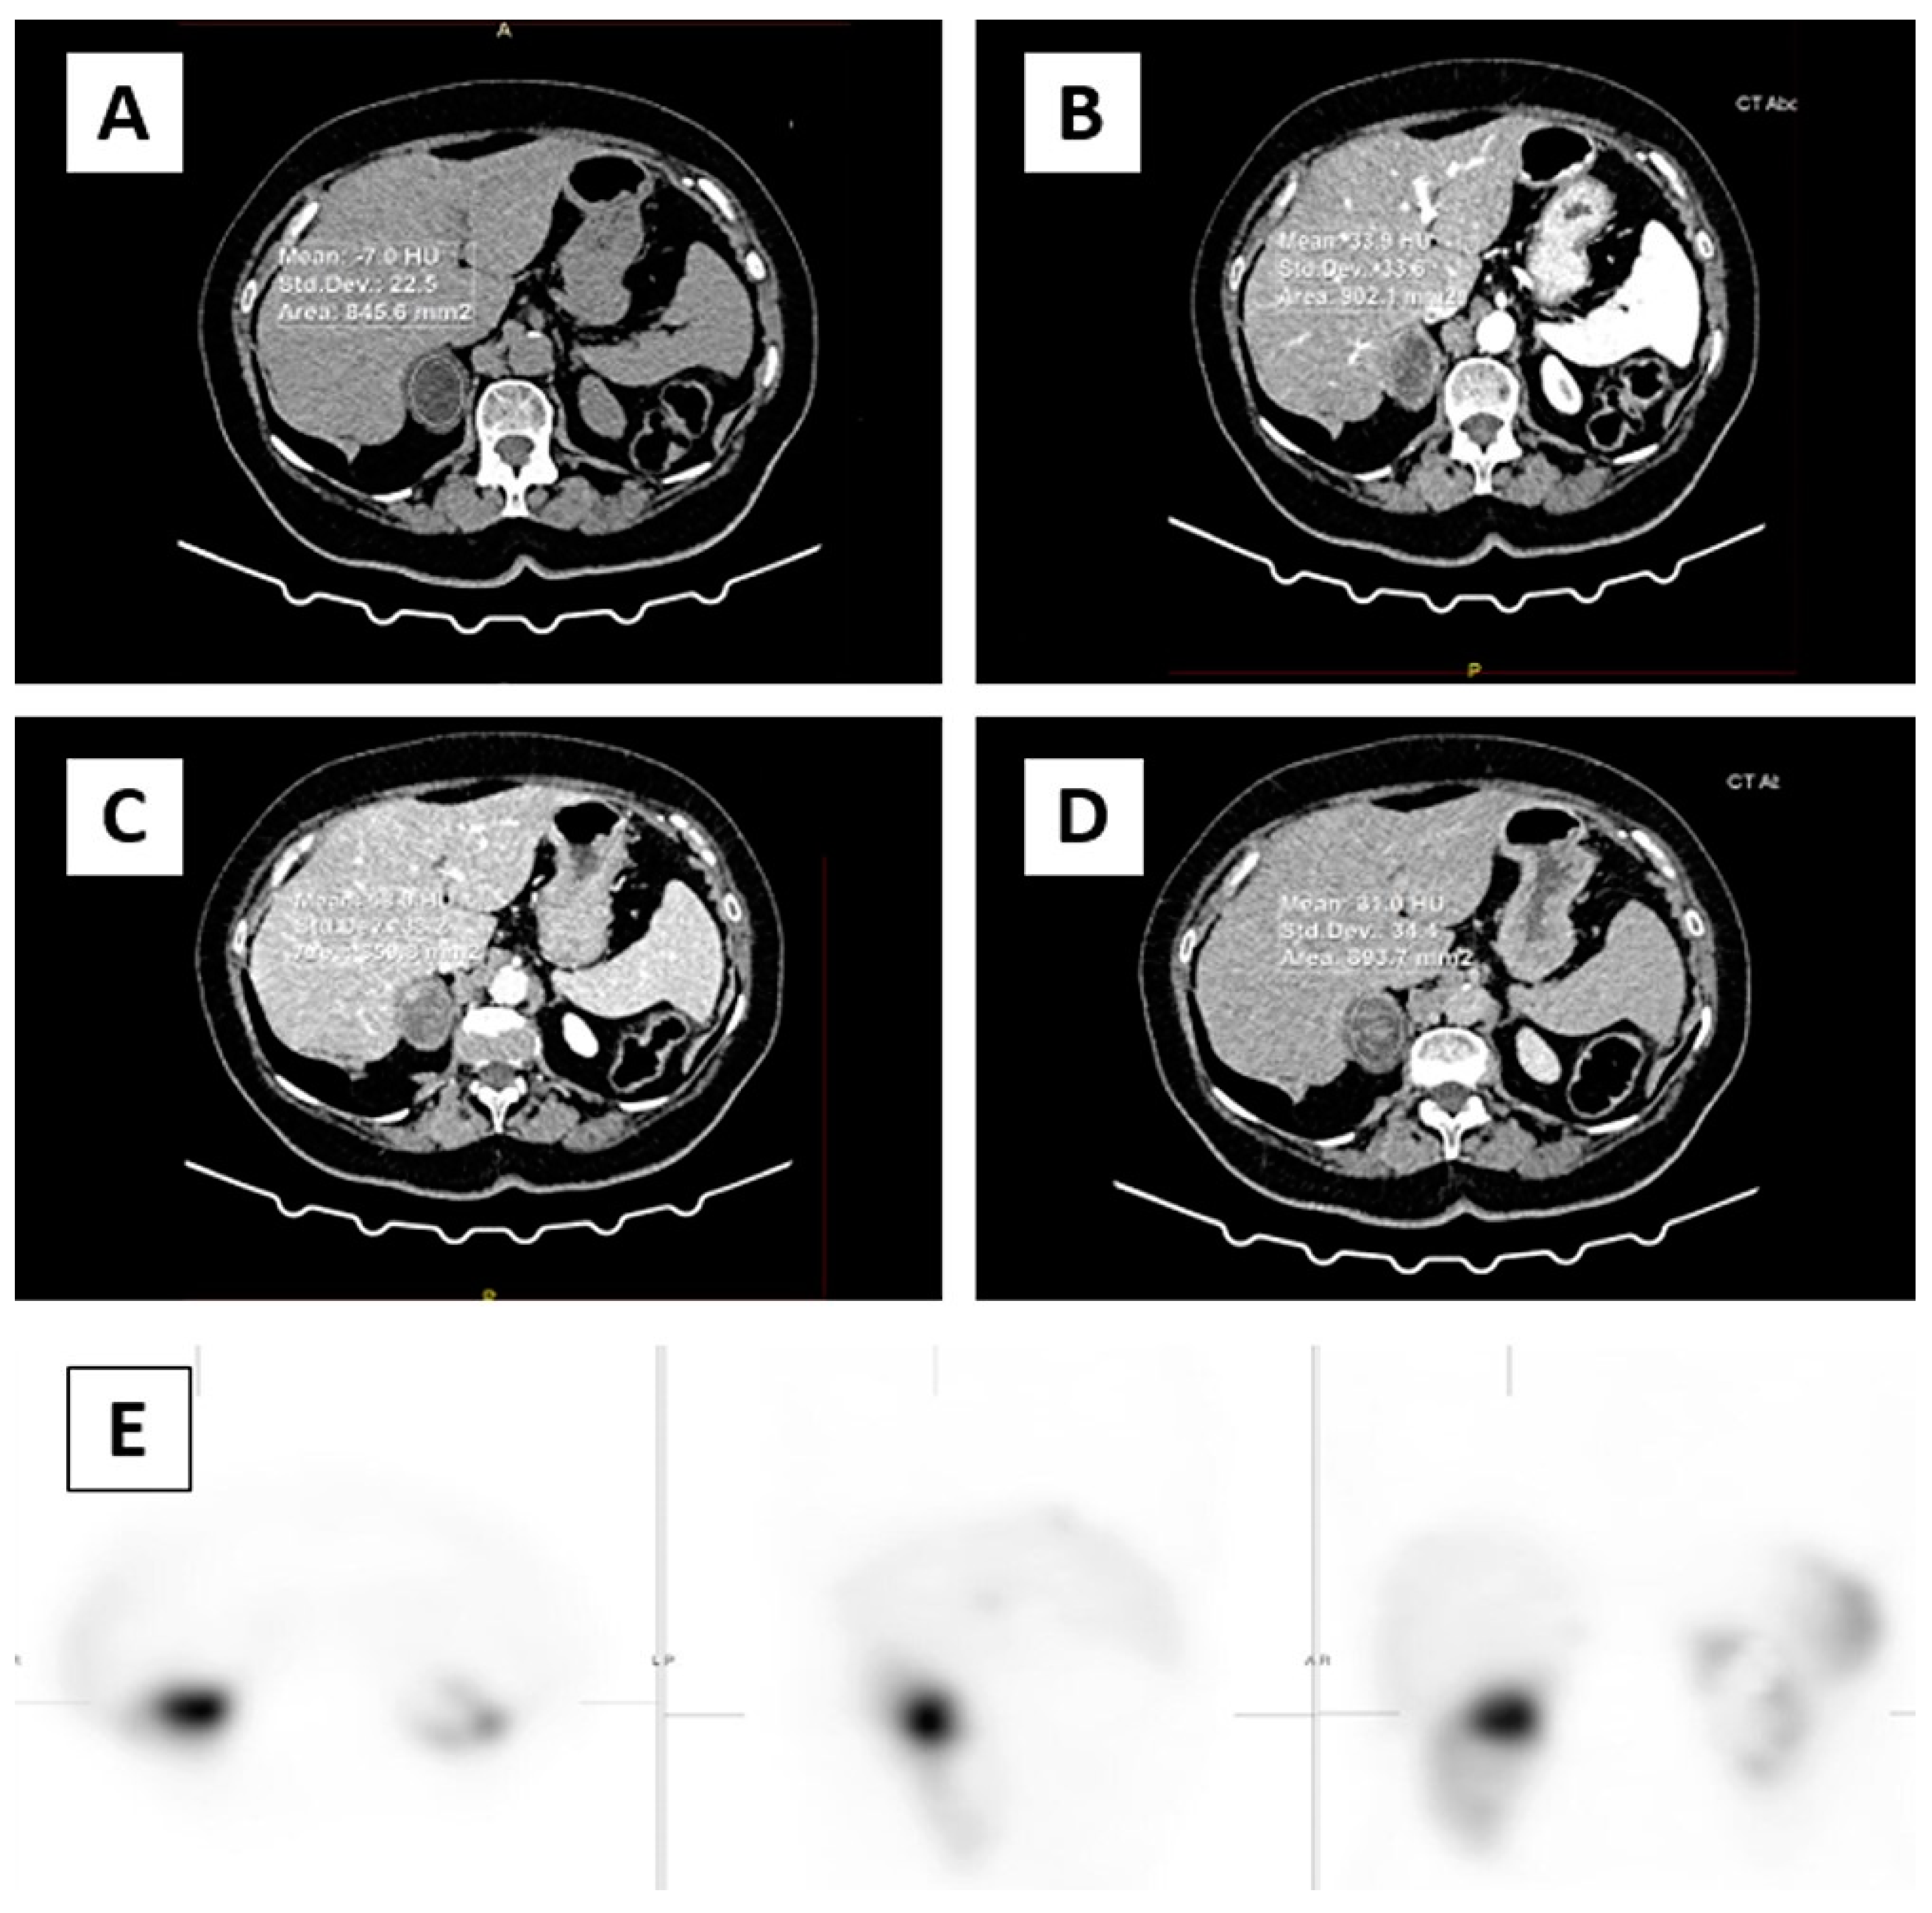

2.4. Nuclear Medicine Imaging Protocol